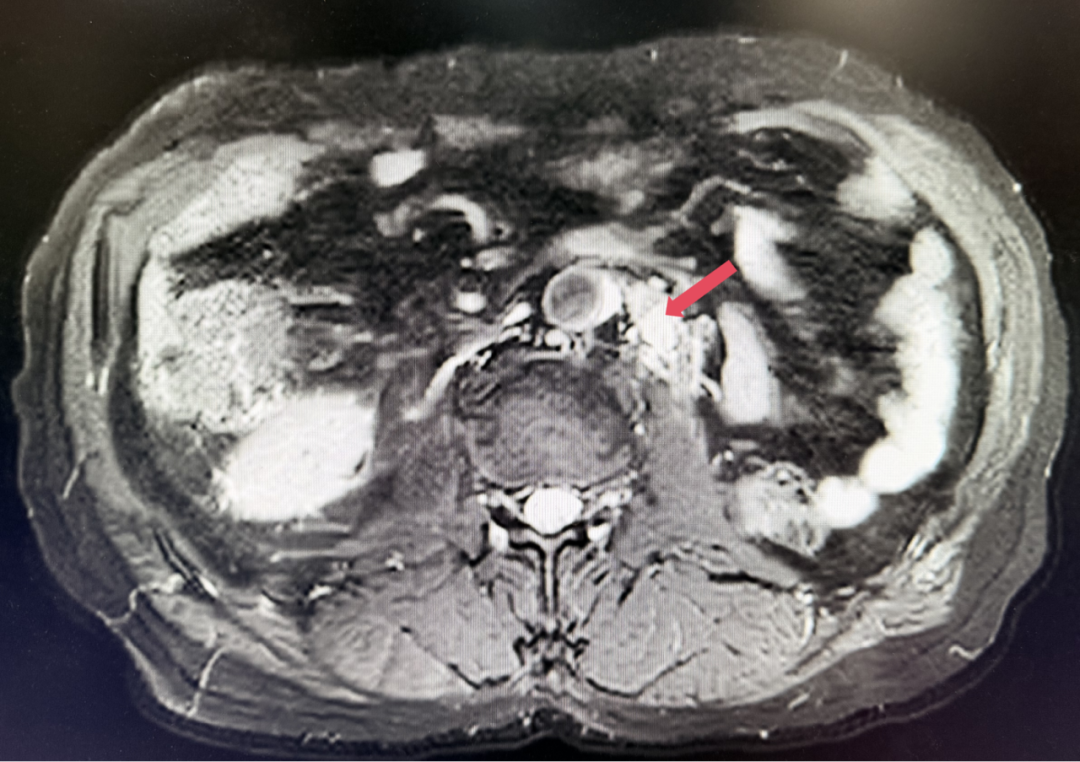

2023年1月开始使用呋喹替尼联合信迪利单抗方案,具体方案为:呋喹替尼5mg,po,qd,D1-14+信迪利单抗200mg,ivgtt,D1,q3w。患者基线肿瘤负荷为128.5mm。

2023年3月:用药6周(C2)后首次肿评,肿瘤负荷减少至76.8mm,达到PR。

2023年1月,基线

2023年3月,初始应答

患者初诊时68岁,2020年9月因“体检发现左肾占位2年”行腹腔镜下左肾根治性切除术,术后病理提示为肾透明细胞癌,pT3aN0M0,未行术后辅助治疗、未规律复查。2022年3月胸腹盆CT示腹膜后转移,IMDC评分0分,低危组。随后予一线培唑帕尼治疗,最佳疗效SD,2022年11月PD。于2023年1月经筛选进入Ⅲ期FRUSICA-2临床研究,开始接受呋喹替尼联合信迪利单抗二线治疗,用药6周(C2)后首次肿评即实现疗效PR(缩瘤率40.2%),用药10个月时缩瘤率近七成(68%),并维持上述水平至今,PFS已经超过37个月,在二线治疗中实现了长期无进展生存。同时,患者对呋喹替尼联合信迪利单抗方案耐受性良好,仅见轻微蛋白尿和偶然腹泻,未见其他不良反应,也未见免疫治疗相关不良反应。该方案有望为TKI经治的晚期肾癌患者带来新的选择,为实现长期生存提供可能性。